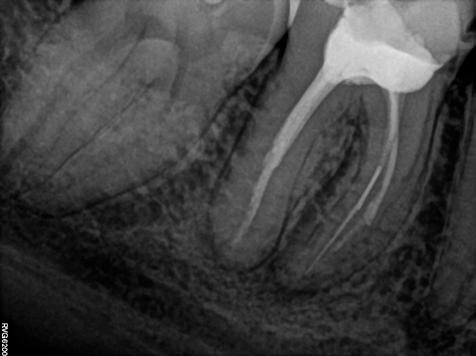

A páciens a jobb alsó első nagyőrlőfogából kiinduló közepes erősségű fájdalom miatt kereste fel a rendelőnket. Periapikális röntgen és CBCT-felvétel is készült. Mindkét felvétel a mesiobukkális gyökércsúcs körül található radiolucens elváltozás jelenlétét igazolta. Ezenfelül a mesialis gyökérben két betört eszközdarab is észlelhető volt. Az egyik a középső gyökéri harmadban a gyökérgörbület előtt volt megtalálható, a másik pedig kicsivel a gyökérgörbület után (12–13. ábra).

12. ábra: A kiindulási CBCT-felvételen jól látható a periapikális felritkulás. – 13. ábra: A kiindulási röntgenfelvételen látható a két betört eszközdarab.